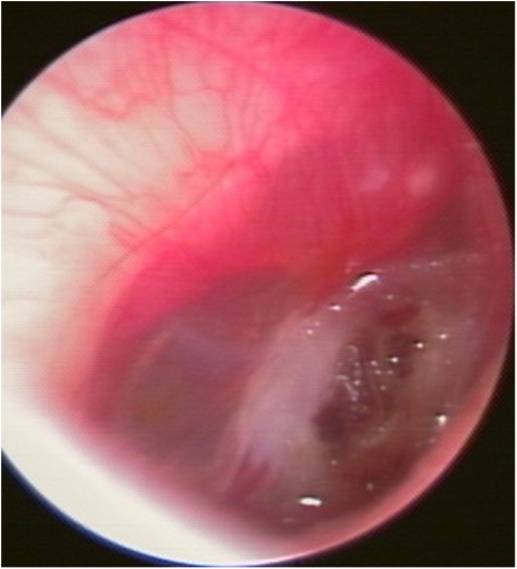

・外力により鼓膜に大きな力がかかり、鼓膜に穴が開いてしまった状態です。

・耳かきでつついた時の用に、直接、鼓膜に外力が及ぶ直達性損傷と、平手打ちなどで圧力がかかり間接的に穴があく、介達性損傷があります。

・鼓膜に穴があくと難聴、耳痛、出血などが生じ、内耳障害を合併すると耳鳴、めまいなども起こします。